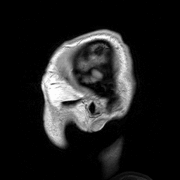

Anatomy is subdivided into gross anatomy (or macroscopic anatomy) and microscopic anatomy. Gross anatomy (also called topographical anatomy, regional anatomy, or anthropotomy) is the study of anatomical structures that can be seen by unaided vision. Microscopic anatomy is the study of minute anatomical structures assisted with microscopes, which includes histology (the study of the organisation of tissues), and cytology (the study of cells).